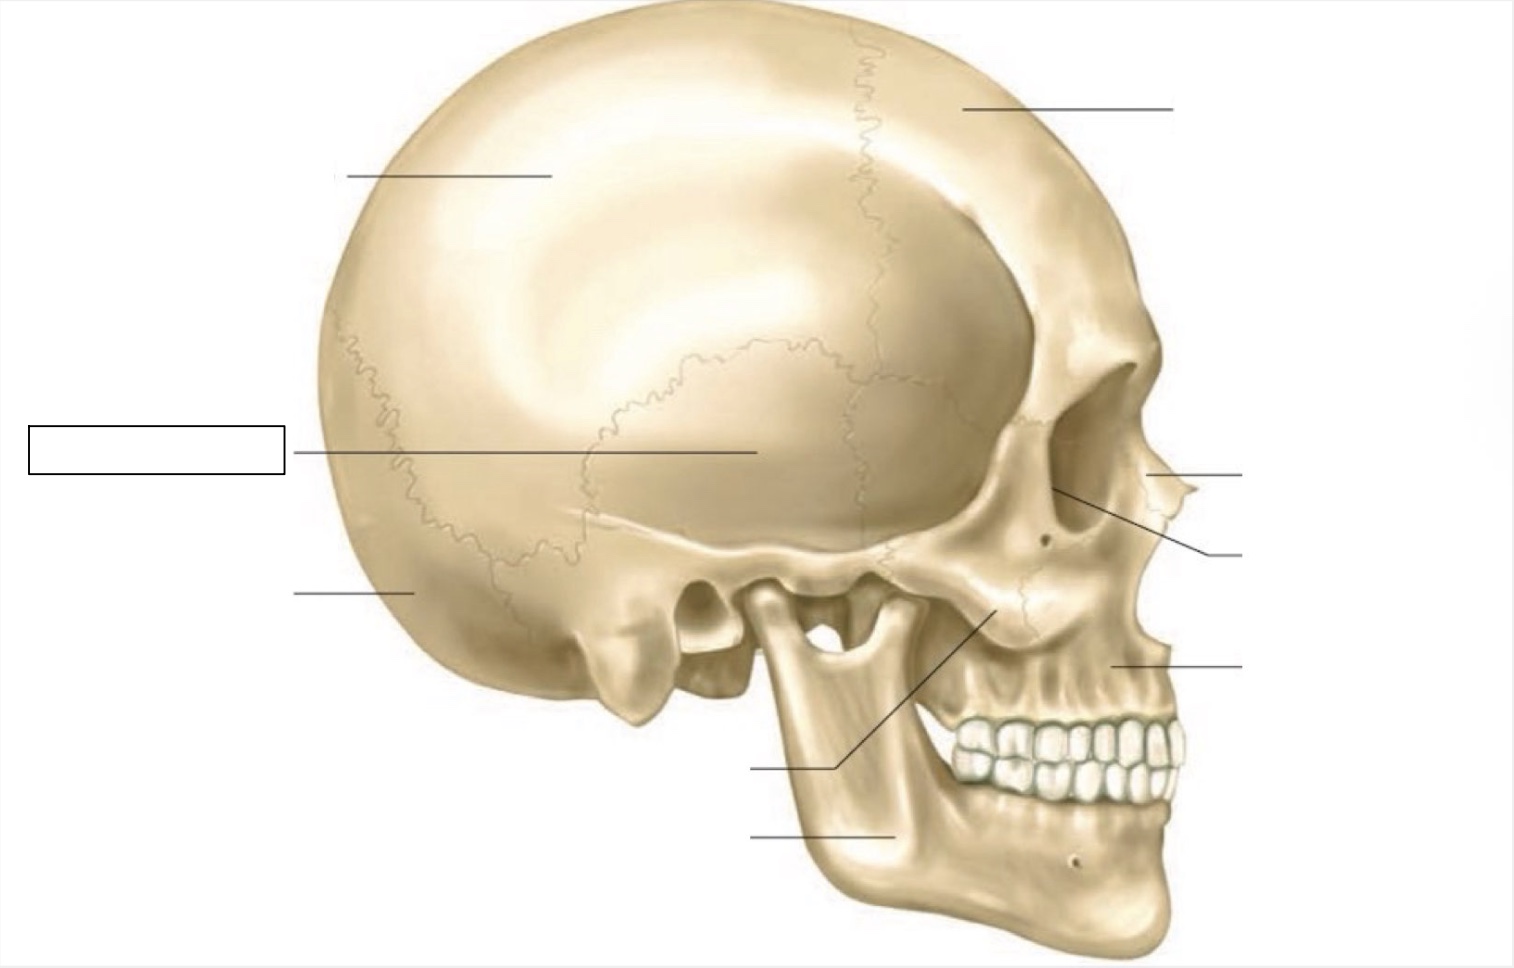

skull

frontal bone

nasal bone

orbit

maxilla

mandible

zygomatic bone

occipital bone

temporal bone

parietal bone